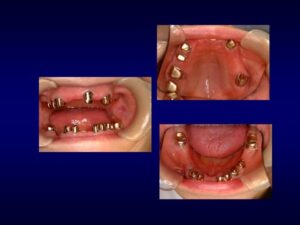

ケース2:上下に多くの問題があった70代後半男性

この方は虫歯や歯周病で残存歯が少なく、グラグラの歯が多い状態でした。最初は保険のクラスプ義歯を入れていたものの安定せず、硬いものを噛めないため外していることが多かったそうです。外見を重視してナイロン義歯を試されましたが、期待したような咬合回復は得られず、全体の再治療を希望して来院されました。

まず全顎の虫歯と歯周病の治療を行い、上顎は残存歯すべてに内冠をかぶせて連結し、全体を支えるテレスコープ義歯を製作しました。装着後は「入れ歯」というよりは取り外し可能な長いブリッジの感覚で、違和感がほとんどないとのことです。

このケースは「残った歯をチーム化して守る」発想が有効であった例です。